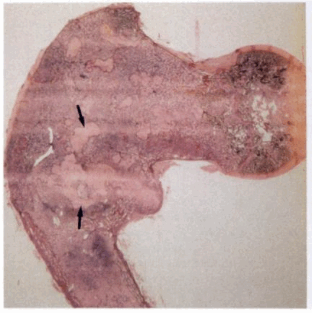

2. Макроскопические и хирургическое особенности:

• Белесые или бежевые очаги зернистой структуры

3. Микроскопия:

• Строма образована рыхлой фиброзной тканью

• Небольшие островки новообразованной кости («азбучный суп»)

• Иногда встречаются фокусы хрящевой ткани